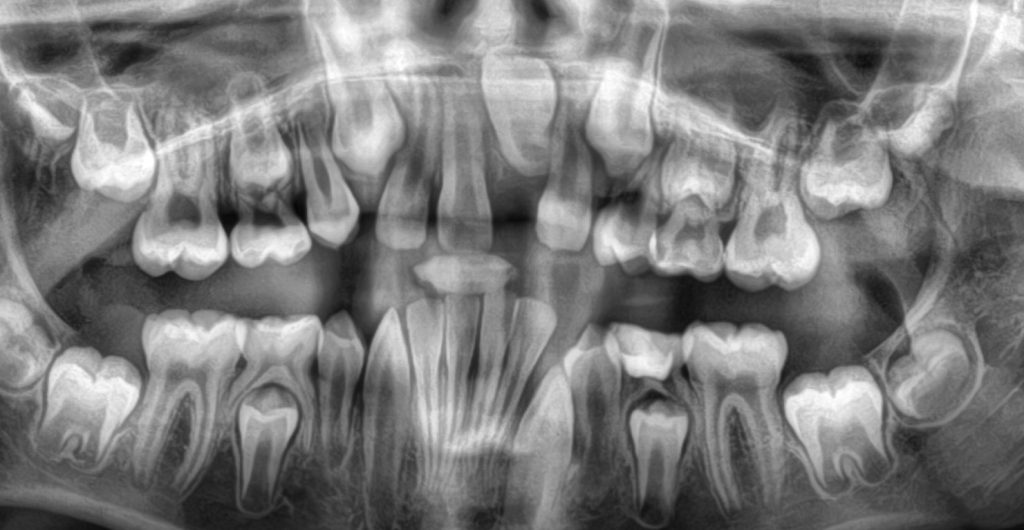

Chirurginės procedūros Chirurginės procedūros odontologijoje apima platų spektrą veiksmų, kurie gali būti reikalingi siekiant gydyti sudėtingus dantų, dantenų, žandikaulių ir burnos sutrikimus (cistų, gerybinių navikų, išdygusių ir neišdygusių dantų šalinimą, implantacijas, kaulo augmentacijos procedūra ir t.t).Burnos ir lūpų cistų, gerybinių navikų šalinimasRetinuotų, virškomplektinių ir kitų dantų bei dantų šaknų šalinimasLiežuvio pasaitėlio plastikaBurnos ir lūpų cistų, gerybinių navikų šalinimasTai chirurginė procedūra, kurios metu pašalinamos cistos, atsiradusios burnos ertmėje ar ant lūpų, bei kiti gerybiniai navikai (fibromos, papilomos, granulomos, lipomos ir pan.) susidarę kauluose arba minkštuosiuose audiniuose, dantų srityje.Cistose dažnai kaupiasi skysčiai, įskaitant pūlius, kurios dažnai susidaro dėl infekcijų, dantų traumų ar kitų priežasčių. Cistų šalinimas gali būti būtinas, siekiant išvengti aplinkinių audinių pažeidimį, infekcijos plitimo ar kaulo pažeidimo.Pradžioje cistos formavimasis dažnai būna nepastebimas, tačiau vėliau pasireiškia kaulo deformacija, patinimu ar net „skylučių“ dantenose atsiradimu, pro kurias išsiskiria pūliai. Dėl šios priežasties cistos dažniausiai nustatomos atsitiktinai, atliekant rentgeno tyrimus dėl kitų sveikatos problemų.Kodėl reikia pašalinti cistas ir auglius?Nors dauguma burnos ir lūpų cistų, mukocelių ir kitų formacijų yra gerybiniai augliai ir nesukelia pavojingų sveikatos problemų, jų pašalinimas gali būti būtinas dėl šių priežasčių:Estetinis diskomfortas: Dauguma pacientų pasirenka chirurginį gydymą dėl estetinių priežasčių, ypač jei formacijos atsiranda matomose vietose (pvz., ant lūpų).Funkciniai sutrikimai: Jei formacija trukdo valgymui, kalbėjimui arba sukelia skausmą, ją gali prireikti pašalinti.Infekcijos prevencija: Kai kurios cistos gali užkrėsti, sukelti uždegimus arba netgi galiausiai virsti piktybiniais navikais, todėl jų pašalinimas padeda išvengti šių komplikacijų.Augimas: Jei cista ar mukocelė auga ir sukelia spaudimą aplinkiniams audiniams, jos pašalinimas gali užkirsti kelią tolesniam pažeidimui.Retinuotų, virškomplektinių dantų ir šaknų šalinimas Tai chirurginė procedūra, kurios metu pašalinami dantys ar jų šaknys, kurios dėl įvairių priežasčių nepavyksta išdygti (išsiveržti) į burnos ertmę, lieka „užstrigusios” žandikaulio kauluose.Kada reikia pašalinti retinuotus ar virškomplektinius dantis?Dantis sukelia skausmą, infekciją ar uždegimą.Dantis sukelia gretimų dantų pažeidimus arba nelygų dantų išsidėstymą.Dantis sukelia cistų ar kitų uždegiminių formacijų susidarymą.Dantis kelia riziką dėl infekcijų (ypač kai jie dalinai prasiveržia ir jų apatinė dalis lieka uždara dantenose).Dantis nebeauga arba jo šalinimas gali pagerinti kitų dantų padėtį (pavyzdžiui, prieš ortodontinį gydymą).Dantų šalinimas yra būtinas, kai:Dantis sukelia skausmą, infekciją ar uždegimą.Dantis sukelia gretimų dantų pažeidimus arba nelygų dantų išsidėstymą.Dantis sukelia cistų ar kitų uždegiminių formacijų susidarymą.Dantis kelia riziką dėl infekcijų (ypač kai jie dalinai prasiveržia ir jų apatinė dalis lieka uždara dantenose).Dantis nebeauga arba jo šalinimas gali pagerinti kitų dantų padėtį (pavyzdžiui, prieš ortodontinį gydymą).Liežuvio ir lūpos pasaitėlio plastikaLiežuvio ir lūpos pasaitėliai (ang. tongue tie) yra maži gleivinės raiščiai, kurie jungia liežuvį su burnos dugnu (liežuvio pasaitėlis) ir viršutinės lūpos pusę su dantenomis (lūpos pasaitėlis). Kai liežuvio pasaitėlis yra per trumpas arba per stipriai įtemptas, tai gali sukelti problemų, pavyzdžiui, sunkumų kalbant ar valgant, arba sunkumų maitinant kūdikį.Jei lūpos pasaitėlis yra per žemas ar storas, jis gali trukdyti tinkamai susiformuoti tarpdančiams, sukelti tarpą tarp priekinių dantų (vadinamą diastema), trukdyti dantų protezavimui arba netgi sukelti kalbos problemų.Jei pasaitėlis trukdo kalbėjimui, valgymui ar kitoms kasdienėms funkcijoms, kartais gali prireikti chirurginio įsikišimo, kad būtų pašalinta dalis pasaitėlio. Tai paprastai yra greita ir nesudėtinga procedūra, vadinama frenotomija.Dažniausiai užduodami klausimai (D.U.K.)Ką daryti, jei įtariate cistą ar naviką?Jei pastebėjote, kad burnoje arba ant lūpų atsirado patinimas, gumbas ar nepaaiškinami skausmai, svarbu kuo greičiau kreiptis į specialistą. Gydytojas atliks išsamų tyrimą (dažnai tai būna biopsija ar ultragarsinis tyrimas) ir pasiūlys geriausią gydymo metodą, priklausomai nuo naviko tipo ir dydžio.Į kurį specialistą kreiptis, jei pajutau burnoje gumbą ar skausmą?Burnos chirurgai ir veido bei žandikaulių specialistai turi didelę patirtį sprendžiant šias ar panašias problemas, todėl pirmiausia reikėtų kreiptis konsultacijai ir detaliasniam ištyrimuiAr danties šalinimas yra skausminga procedūra?Danties šalinimas (ekstrakcija) yra dažna odontologinė procedūra. Dažnu atveju atliekant danties šalinimą, pacientai patiria tik minimalų diskomfortą, nes procedūros metu naudojamos vietinės anestezijos priemonės. Tačiau, kaip ir su bet kokia chirurgine procedūra, kiekvienas žmogus gali jausti skirtingą skausmą ir diskomfortą priklausomai nuo danties būklės ir sudėtingumo.Kodėl reikia pašalinti cistas ir auglius?Nors dauguma burnos ir lūpų cistų, mukocelių ir kiti dariniai yra gerybiniai augliai ir nesukelia pavojingų sveikatos problemų, jų pašalinimas gali būti būtinas dėl šių priežasčių: jei trukdo valgymui, kalbėjimui arba sukelia skausmą, dėl infekcijos plitimo bei augimo bei dėl estetinių priežasčių.Kodėl atsiranda liežuvio pasaitėlio patologija?Liežuvio pasaitėlio patologija dažnai yra įgimta būklė, kurią gali sukelti genetiniai faktoriai arba netinkamas burnos vystymasis. Tai gali sukelti kalbos, maitinimo ir burnos higienos problemas. Chirurginis gydymas gali būti veiksmingas būdas, siekiant pašalinti šias problemas ir pagerinti gyvenimo kokybę. Svarbu pasitarti su specialistu, jei pastebite, kad liežuvio judėjimas yra ribotas arba yra sunkumų kalbant ar valgant.Kaip atliekama retinuotų dantų šalinimo procedūra?Dantų šalinimas yra sudėtinga chirurginė procedūra, kuri dažnai atliekama vietinėje anestezijoje. Kai kuriais atvejais, jei dantis labai gilus ar sunkiai prieinamas, gali prireikti bendrosios nejautros.Registruokitės šiai paslaugai dabar Internetu +370 444 77777 Paslaugos specialistai Visi Kaunas Vilkaviškis Visi specialistai Shahaf Givony Gyd. burnos chirurgasKaunas Rasa Pedišienė Gyd. burnos chirurgėKaunas, Vilnius Justinas Bardijevskis Implantuojantis ir protezuojantis gyd. odontologasKaunas, Vilkaviškis Gabrielė Berniūtė Gyd. odontologė, specializuojasi dantų šalinimeKaunas Otilija Lieščinskaitė Gyd. odontologė, specializuojasi dantų šalinimeKaunas Greta Milvydaitė Gyd. odontologė, specializuojasi dantų šalinimeVilkaviškis Shahaf Givony Gyd. burnos chirurgasKaunas Rasa Pedišienė Gyd. burnos chirurgėKaunas, Vilnius Justinas Bardijevskis Implantuojantis ir protezuojantis gyd. odontologasKaunas, Vilkaviškis Gabrielė Berniūtė Gyd. odontologė, specializuojasi dantų šalinimeKaunas Otilija Lieščinskaitė Gyd. odontologė, specializuojasi dantų šalinimeKaunas Justinas Bardijevskis Implantuojantis ir protezuojantis gyd. odontologasKaunas, Vilkaviškis Greta Milvydaitė Gyd. odontologė, specializuojasi dantų šalinimeVilkaviškis